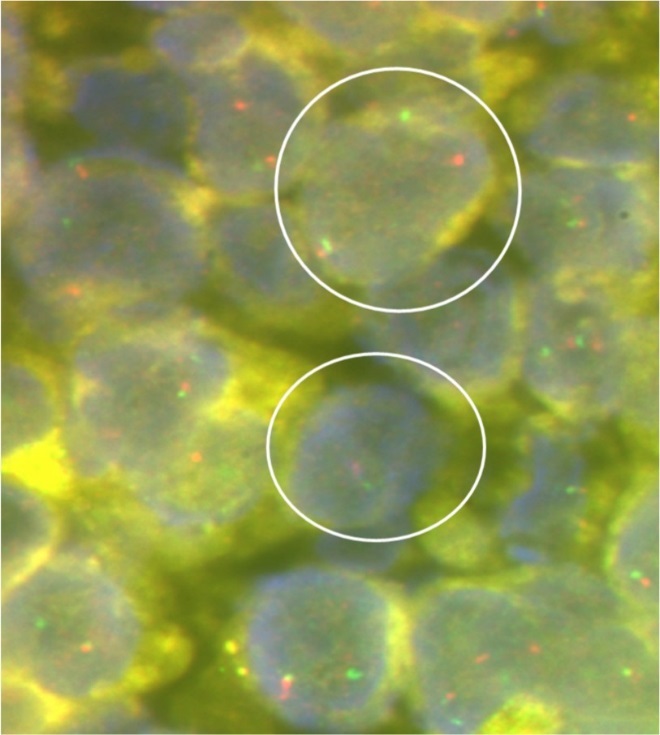

A J-needle biopsy from the extremity tumor showed the tumor to be composed of ‘undifferentiated small blue round cells’ (Figure 3A) with variable cytoplasmic vacuolation. To characterize the lesion further, appropriate special stains and IHC was carried out on the biopsy specimen. The vacuolated cells stained positive for Periodic Acid Schiff (Figure 3B) while the small blue round cells were diffusely membrane positive for CD99 or Mic2 (Figure 3C), focally weak positive for FLI-1, and negative for LCA and desmin suggesting a primary ES/PNET rather than metastases from medulloblastoma. To aid in definitive diagnosis, molecular testing was done showing Ewing’s sarcoma breakpoint region 1 (EWSR1) gene re-arrangement (Figure 4) on fluorescence in-situ hybridization (FISH). Ewing’s sarcoma is strongly associated with translocation t(11;22) in most cases4 and t(7;22) or t(21;22) in some cases, all involving the EWSR1 gene on chromosome 22.

Figure 4.Representative photomicrograph of interphase fluorescence in-situ hybridisation (FISH) for Ewing’s sarcoma breakpoint region 1 (Vysis EWSR1 dual colour break apart kit; Abbott Molecular Inc.) showing spilt red and green signals (as shown by the encircled circles) indicating EWSR1 gene re-arrangement strongly supportive of a diagnosis of Ewing’s sarcoma